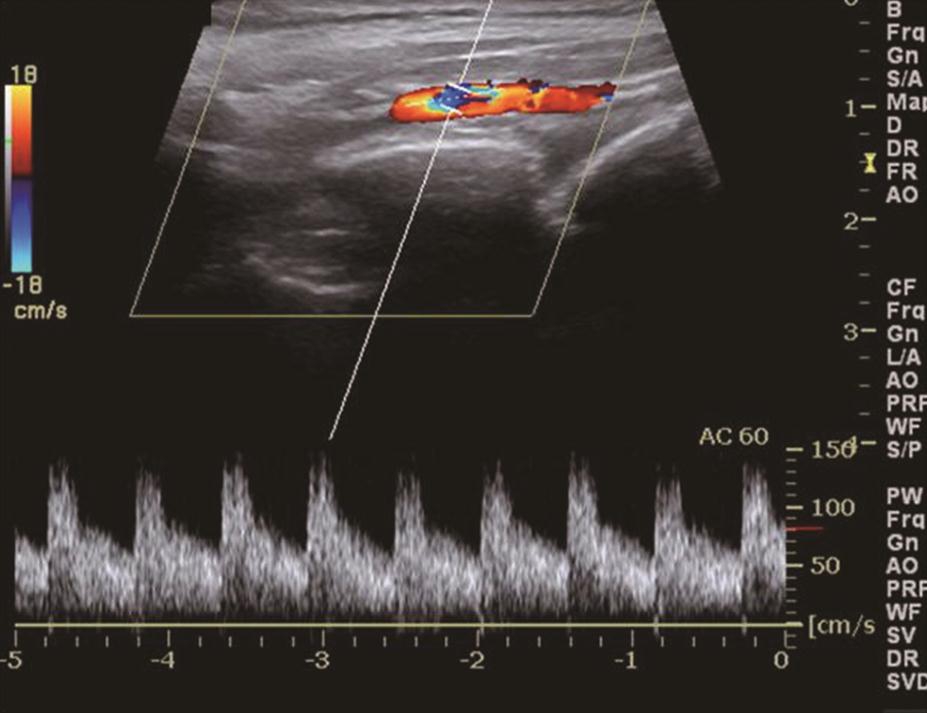

甲状腺呈弥漫性、对称性增大,包膜规则。腺体回声因病程和治疗情况而有所不同。未经治疗者,腺体回声均匀减低,少数呈散在、局灶性减低;病程长及反复发作者,腺体回声正常或稍强。腺体内可见多个管状无回声区(血管扩张)。彩色多普勒显示甲状腺内血流信号极为丰富,呈“火海征”(图3)。频谱多普勒可见甲状腺上、下动脉血流速加快,收缩期峰值流速多超过70cm/s(正常为30cm/s)(图4)。

图4与图3同一患者,右侧甲状腺上动脉收缩期峰值流速高达140cm/s